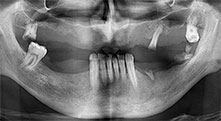

Bratu: Utilizamos los insertos de forma rutinaria para la extracción de injertos óseos y la ranuración de las crestas alveolares. También utilizamos las Piezomed B6/B7 para practicar osteotomías en dientes retenidos y no retiramos implantes que pueden conservarse. Todas estas son indicaciones que requieren cortes profundos y limpios.

Bratu: Preferimos realizar las osteotomías en la línea oblicua externa de la cara posterior del maxilar inferior, y no en la región situada entre los orificios. Tras realizar una incisión en los tejidos blandos, utilizamos las nuevas sierras para definir el contorno de la osteotomía. De este modo, conseguimos una preparación completa en prácticamente el 80 por ciento de los casos. Por otro lado, en algunas ocasiones también utilizamos otros insertos piezoquirúrgicos, así como un cincel para mover el injerto. Para nosotros, esta es una técnica de intervención muy eficaz.

En su clínica de Timisoara se realizan sobre todo intervenciones quirúrgicas orales y procedimientos protésicos y reconstructivos, donde se concede una importancia especial a la implantología. ¿Utiliza su equipo Piezomed también para otras indicaciones?

Bratu: También utilizamos el equipo Piezomed para alargamientos quirúrgicos de coronas y en la cirugía periodontal.